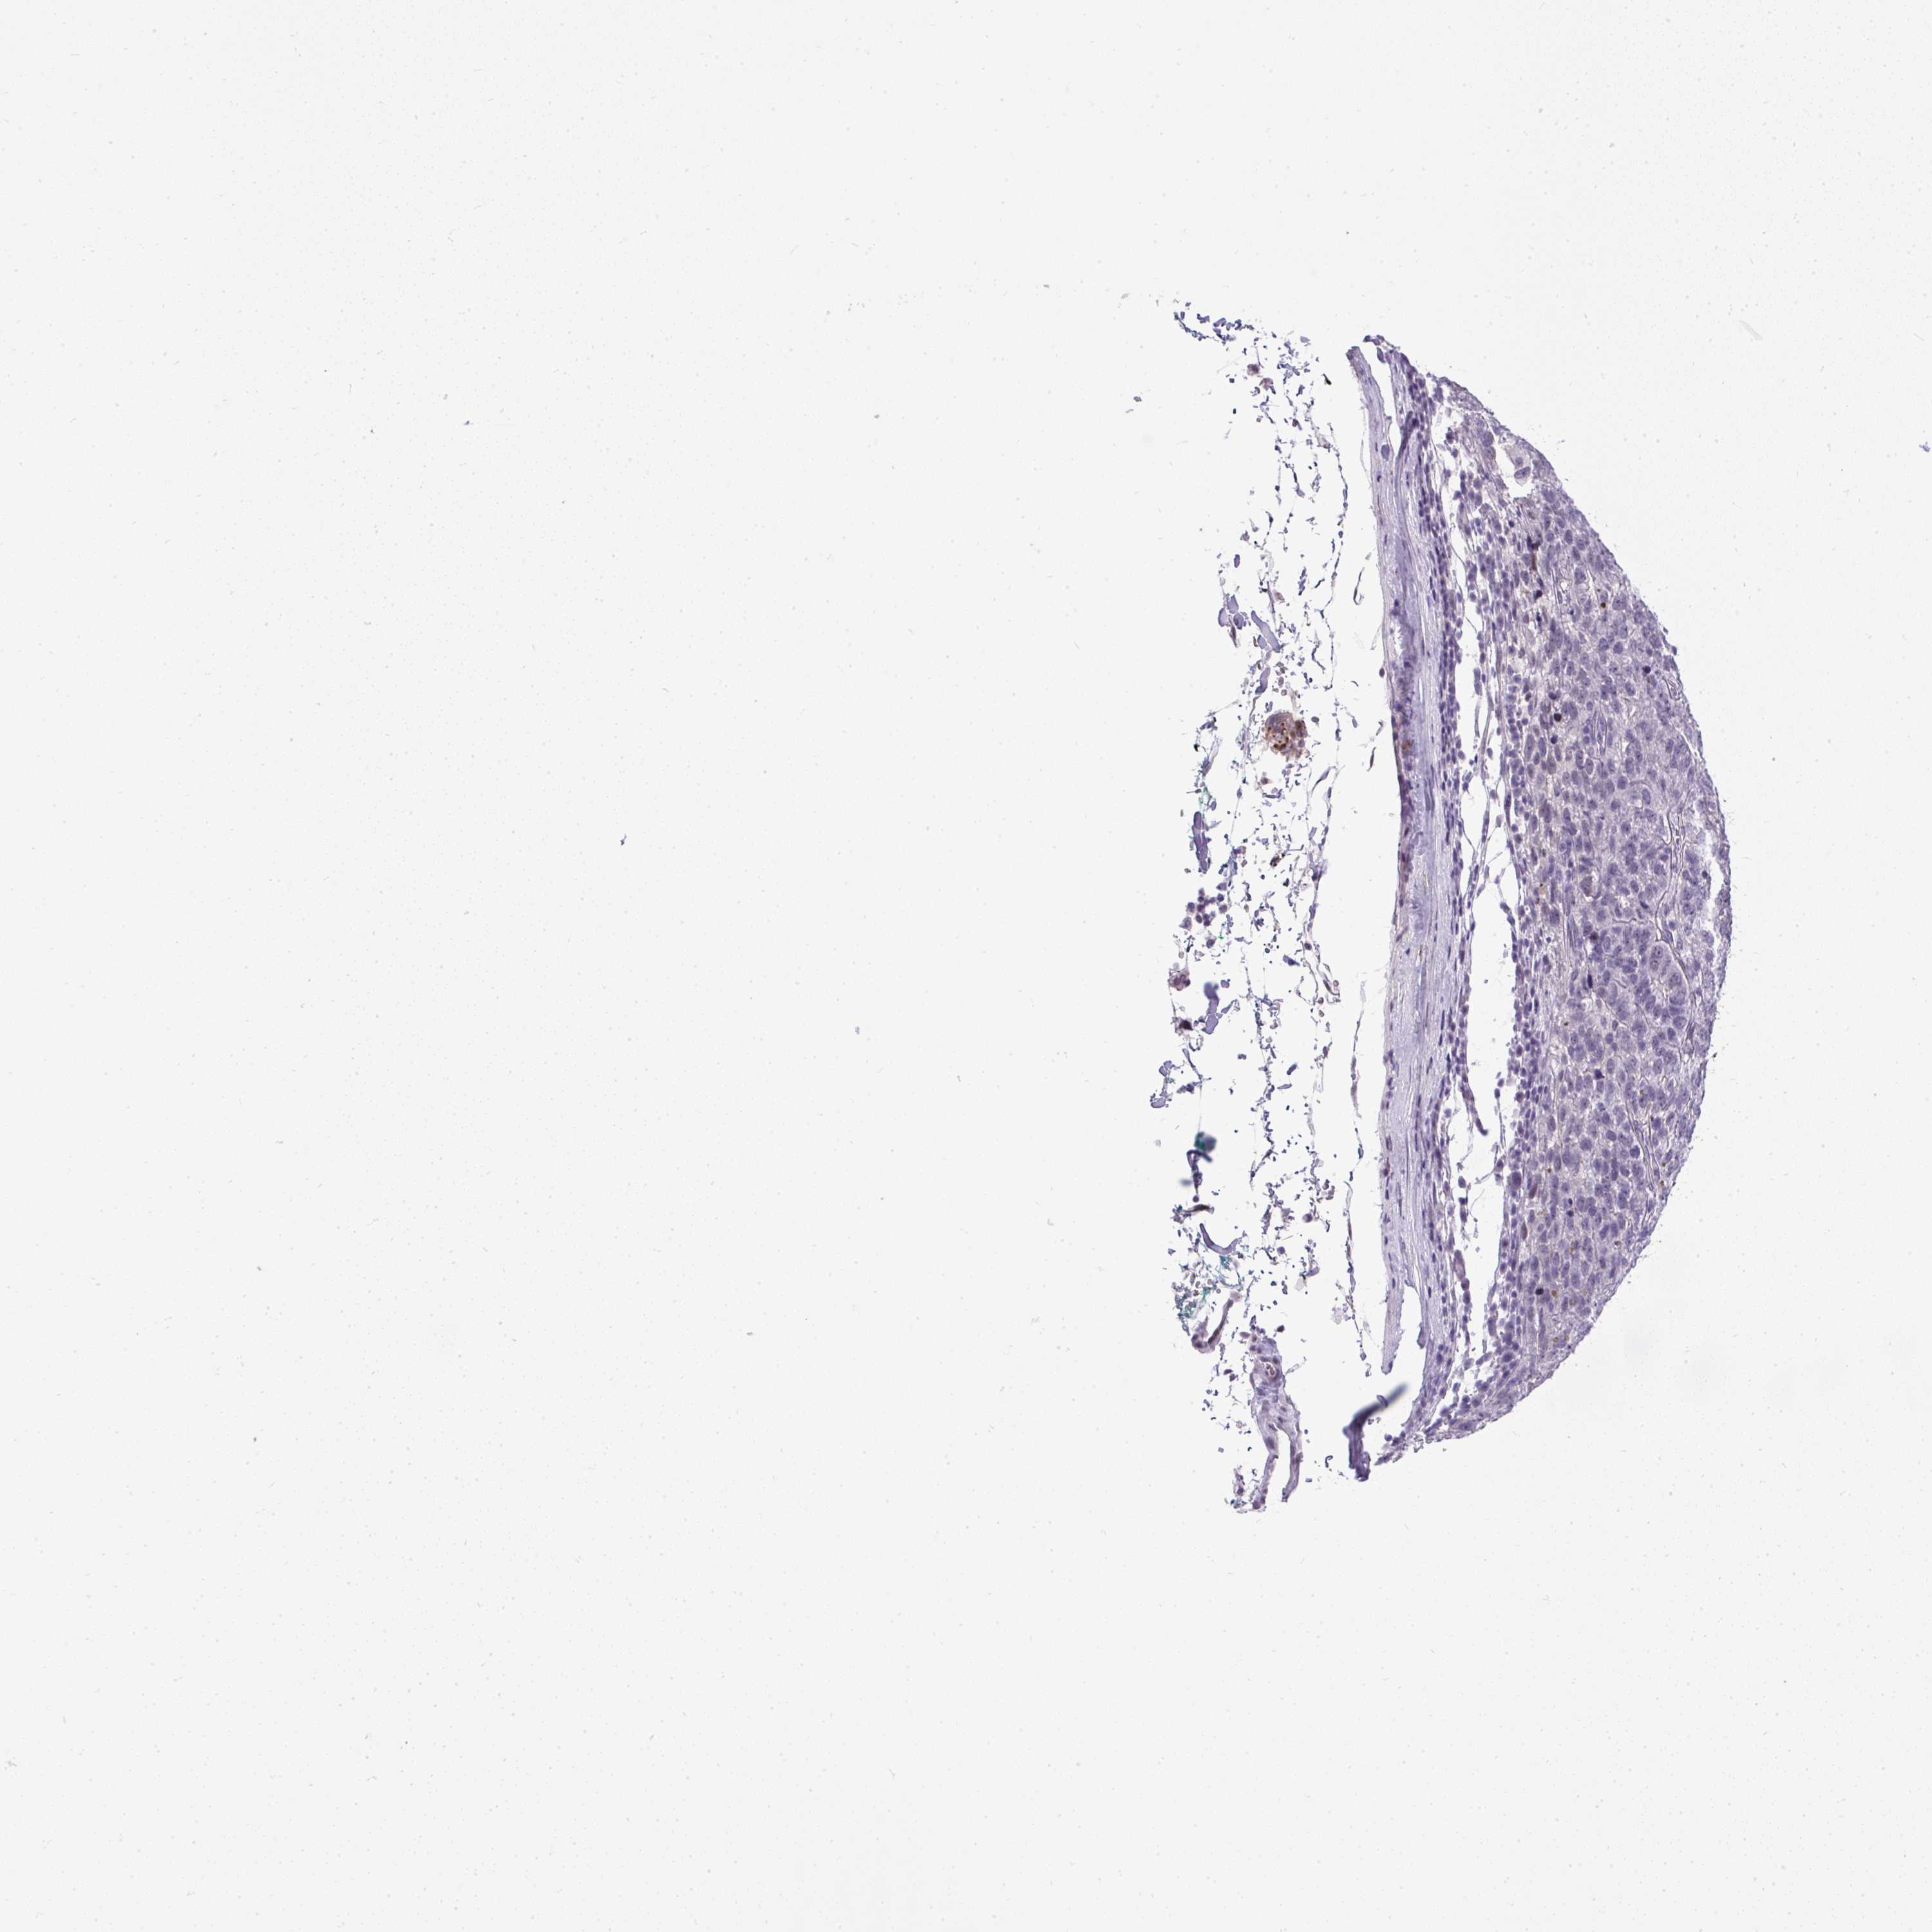

PANCREATIC CANCER - Protein expressioni

A mouse-over function shows sample information and annotation data. Click on an image to view it in a full screen mode. Samples can be filtered based on level of antibody staining by selecting one or several of the following categories: high, medium, low and not detected. The assay and annotation is described here.

Note that samples used for immunohistochemistry by the Human Protein Atlas do not correspond to samples in the TCGA dataset.

Antibody stainingi

Antibody staining in the annotated cell types in the current human tissue is reported as not detected, low, medium, or high, based on conventional immunohistochemistry profiling in selected tissues. This score is based on the combination of the staining intensity and fraction of stained cells.

Each image is clickable and will lead to virtual microscopy that enables deeper exploration of all samples and also displays staining intensity scores, fraction scores and subcellular localization as well as patient and tissue information for each sample.

Antibody HPA055048

Staining

High

Medium

Low

Not detected

Intensity

Strong

Moderate

Weak

Negative

Quantity

>75%

75%-25%

<25%

None

Location

Nuclear

Cytoplasmic/membranous

Cytoplasmic/membranous,nuclear

Adenocarcinoma, NOS